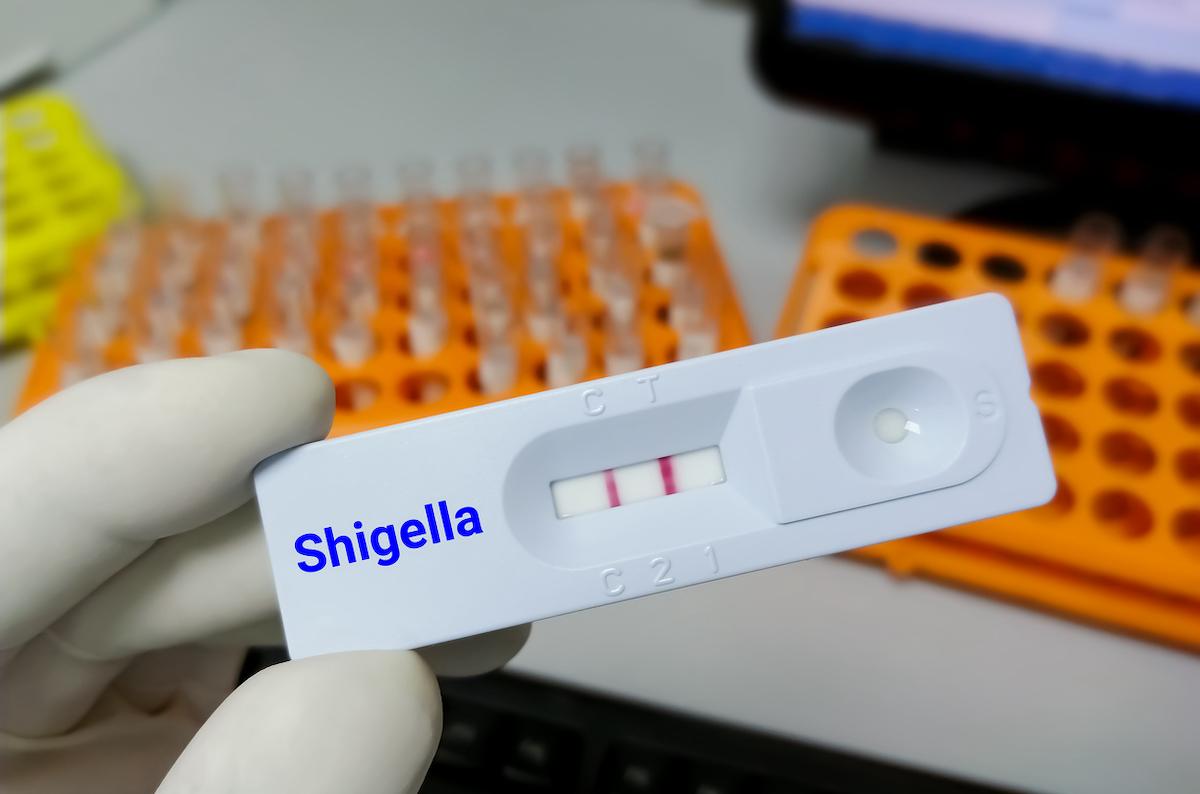

- Md Saiful Islam Khan/istock

En effet, au 16 février 2023, 221 cas de shigellose, principalement à Shigella sonnei, ont été confirmés dans 10 pays européens, le Royaume-Uni et les Etats-Unis. Et 37 cas suspects ont également été détectés. Tous revenaient du Cap Vert.

Une bactérie résistante

Côté traitement, la principale souche retrouvée, Shigella sonnei, oriente vers une résistance au triméthoprime et à la streptomycine. Toutefois, des cas de multirésistance ont déjà été détectés.